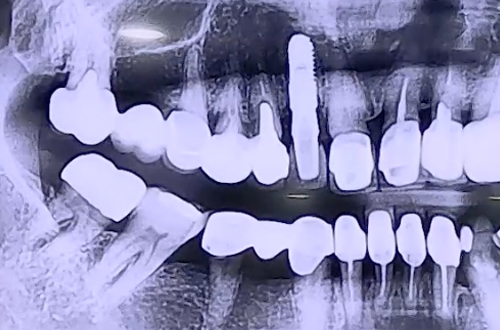

AFTER

보철의 구조와 치료가 필요한 앞니의 상태가 발치를 한 뒤 임플란트를

진행해야 하는 상황이었기 때문에 앞니 보철을 절단하고 임플란트를 해 드렸습니다.

앞니이기 때문에 잇몸 모양까지 자연스럽게 해 주기 위하여 임플란트 식립과

임시치아를 제작하고 붙일 때의 잇몸 모양까지 신경을 썼고

최종 보철까지 예쁘게 완성되었던 사례입니다.